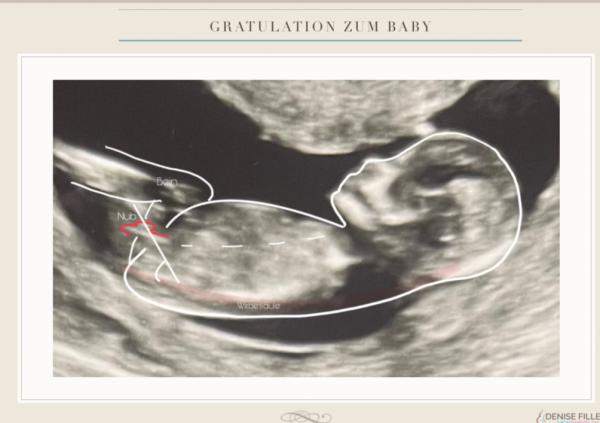

Das ist so unglaublich lieb von dir das du dir so viel Mühe gibst wirklich 😊❤️ Ich habe das Bild an eine Nub Expertin gesendet ich weiß zwar nicht  wie zuverlässig die wirklich sind aber sie hat mir tatsächlich den Nub da eingezeichnet wo du ihn auch eingezeichnet hast 😅 Ich hänge dir das Bild mal an. Villeicht solltest du überlegen nebenberuflich auch so eine Plattform zu eröffnen du hast das wirklich exakt so eingezeichnet😅 vielen Dank. Ich gebe dir aufjedenfall ein Update wenn ich ein outing habe allerdings habe ich den nächsten Termin erst am 23.01 Liebe Grüße

Bild zu

Ich war einfach mal so frei in deinen Bildern ein zu zeichnen, warum du unterschiedliche Nubs von den Leuten gesagt bekommst.  Dieses erste Bild sieht halt doch schon sehr nach Jungen aus. Über dem vermeindlichen Nub noch dieser kleine Strich und es steht recht hoch und nicht so sehr parallel zur Wirbelsäule    Das zweite Bild, da habe ich dir die suuuper leicht angedeutete Gabelung gezeigt, die ich meine.  Gucke mir jetzt deine Bilder auch nicht weiter an 😂😂😂. Bin echt richtig hin und her gerissen